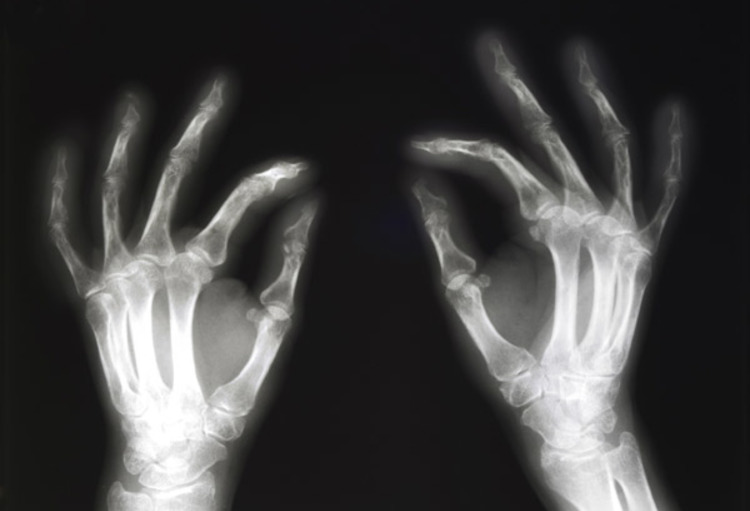

Arthritis and Rheumatoid Arthritis may cause joint deformities, cracking sounds, instability, catching sensations, and pseudo-locking of the joints as they progress.

As joints are repeatedly used, cartilage gradually wears down. Eventually, cartilage may disappear completely, leaving the bone exposed. These diseases can affect the spine, and the joints most commonly involved are those of the hands, wrists, hips, knees, and feet.